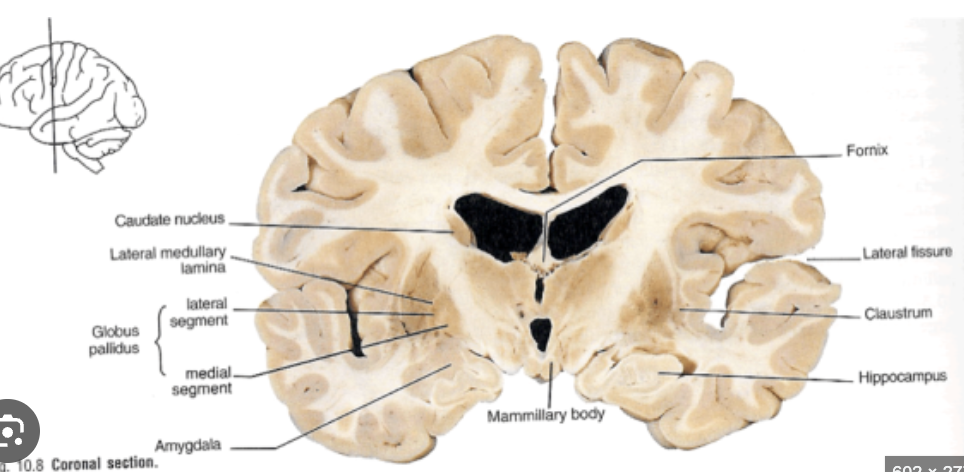

Hippocampus VS amygdala

Thalamus & Caudate & Putamen & Internal capsule & red nucleus & crus cerebri & corticospinal fibres

Caudate & putamen & external globus palidus & internal gobus palidus & mamilary bodies